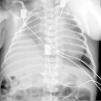

Presentamos el caso de un neonato de 9 días de vida, que ingresa en la Unidad de Cuidados Intensivos Pediátricos para asistencia con circulación con membrana extracorpórea veno-arterial (ECMO-VA) después de cirugía correctora de eventración diafragmática y reparación de hipoplasia de arco aórtico.

La paciente presentó insuficiencia respiratoria aguda hipoxémica grave de forma progresiva. Se estabilizó y a los 9 días de vida se realizó cirugía de la eventración diafragmática (mediante toracotomía lateral) y corrección de la hipoplasia de arco (a través de esternotomía media con circulación extracorpórea). Presentó múltiples arritmias y disfunción severa del ventrículo derecho, siendo necesario soporte con ECMO-VA.

Posteriormente, presentó mala evolución a nivel respiratorio a pesar del soporte con ECMO-VA, tratamiento con óxido nítrico, epoprostenol, surfactante y ventilación de alta frecuencia oscilatoria. A nivel hemodinámico, presentó múltiples episodios de taquicardia ventricular y fibrilación ventricular (fig. 2), realizándose estudio electrofisiológico en 2 ocasiones, en los que se ablacionaron 2 vías de reentrada auriculoventricular antidrómica. La paciente persistió con arritmia intratable, disfunción biventricular severa y fallo multiorgánico progresivo. Dadas las lesiones asociadas y la mala evolución, se decidió retirar los tratamientos de soporte vital de acuerdo con la familia, se limitó el esfuerzo terapéutico. La paciente falleció a los 36 días de vida. Se realizó el estudio autópsico para documentar las malformaciones e intentar esclarecer el diagnóstico.